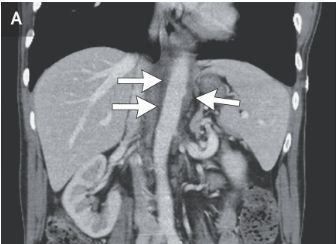

Recent research and publications have underscored the use, efficacy, safety and limitations to the use of cannabis for arthritis and pain patients.

Chronic pain affects more than one in five American adults, yet practitioners are limited in treatment alternatives. Even if we exclude the